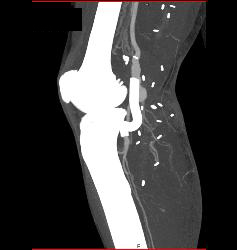

Hematoma Around Stent in Popliteal Artery. Stent Is Partially Occluded